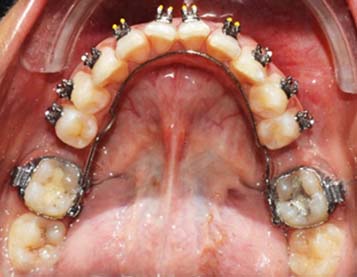

After levelling and alligning the upper arch, lower arch bonding was done. Wilson’s 3D lingual arch was fabricated and inserted in the lower arch [Table/Fig-12].

Insertion of the Wilson’s 3D lingual arch to upright the second molars bilaterally.